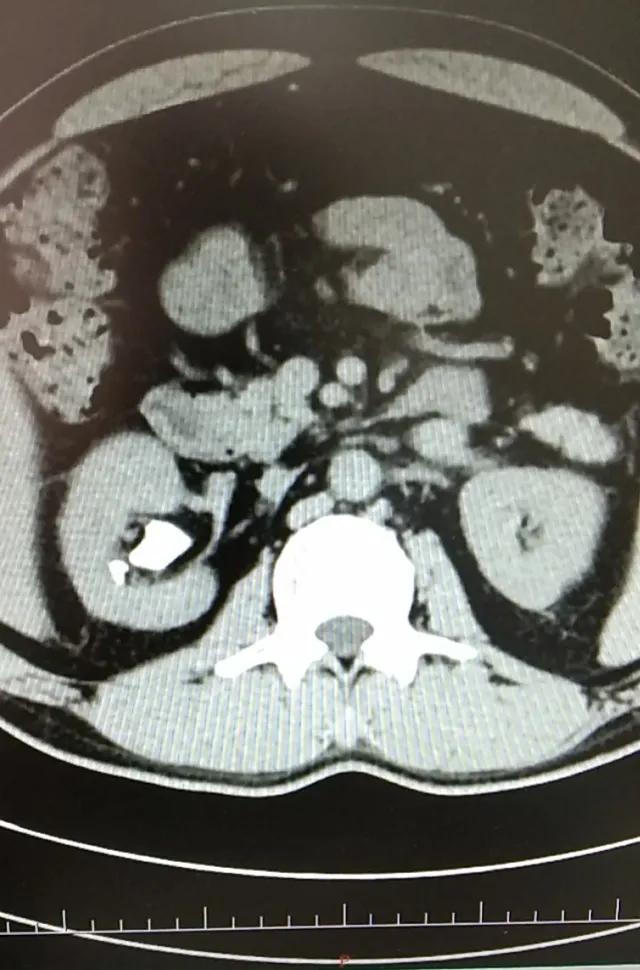

术前X光片